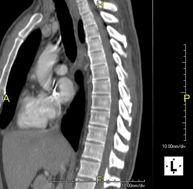

Thoracic spine CT

Radiological test that involves capturing high-definition anatomical images of the thoracic vertebrae using a CT (computed tomography) scanner. Indicated for: back pain, study of spinal deviations, trauma.